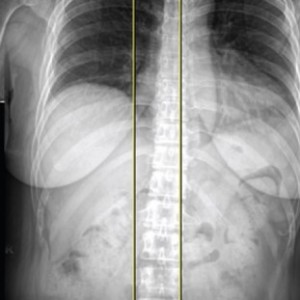

▲ 무릎 수술환자의 스캐노그램 엑스레이 검사